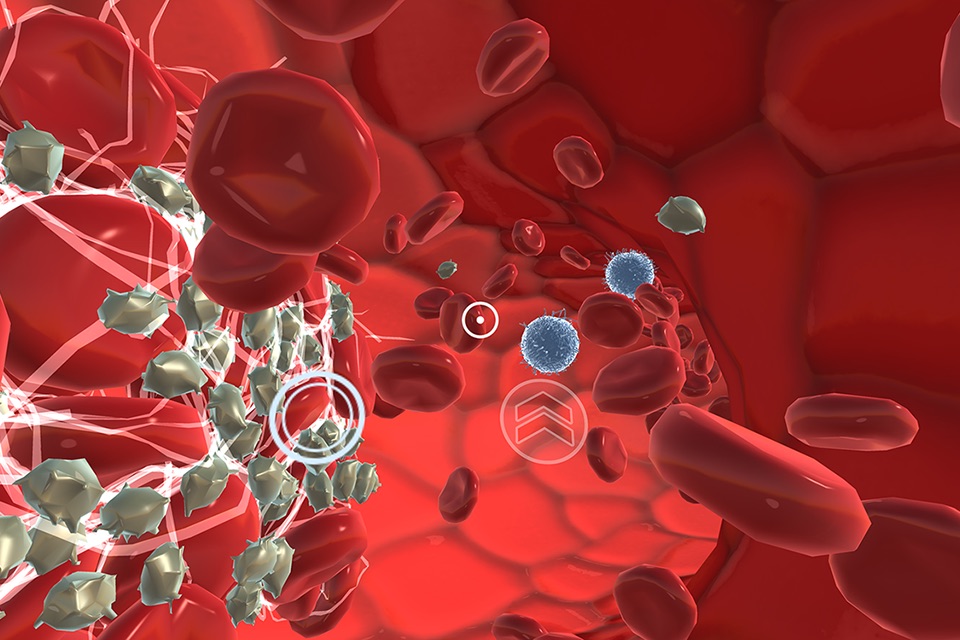

The INVIVO Bloodstream and CNS Explorer is a virtual reality experience designed for Touchscreens and Google Cardboard.

The combination of INVIVO’s world-class 3D content and technical expertise has created a virtual environment like no other. An immersive educational experience, Bloodstream and CNS Explorer transports you to the interior of a blood vessel or into the CNS to learn about human anatomy from an impossible viewpoint.